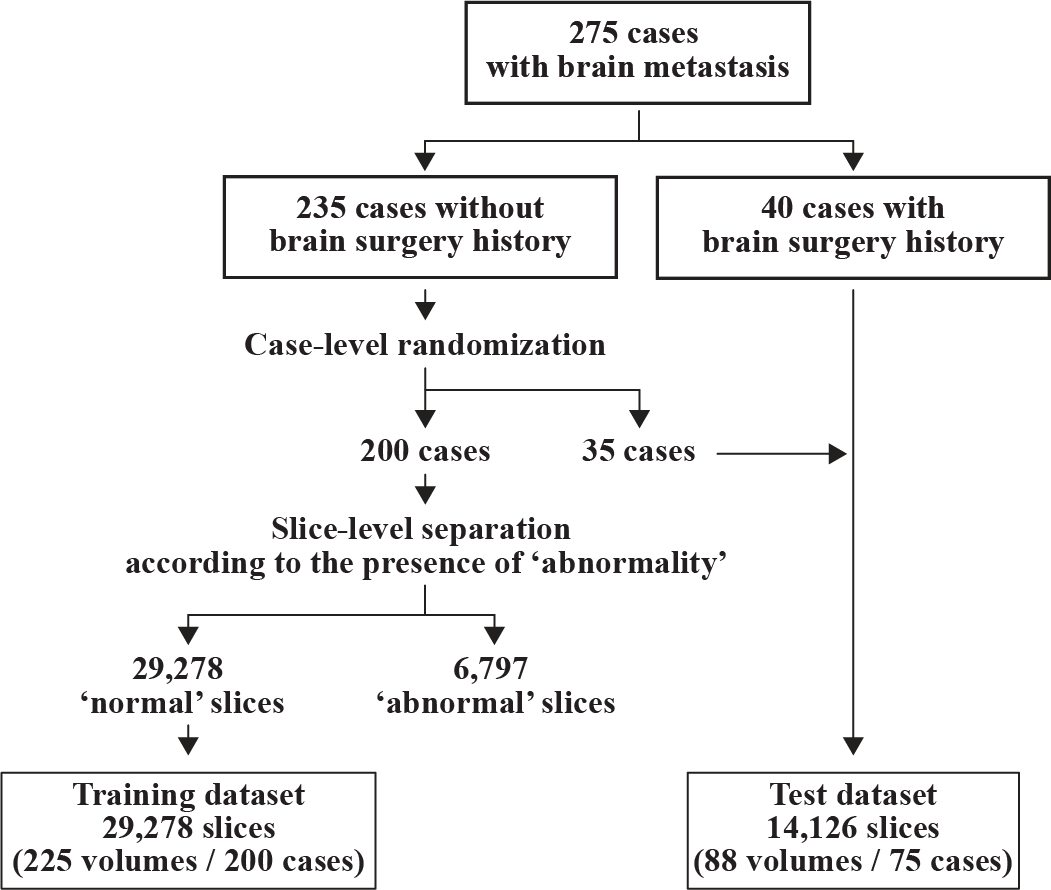

This retrospective, single-center study was approved by our institutional review board. We randomly collected data for 275 patients who underwent MRI analysis for the treatment planning of stereotactic radiotherapy or radiosurgery for brain metastasis using CyberKnife (Accuray Inc., Sunnyvale, CA) during a particular period in our institution. In some cases, several MRI analyses were performed during the study period; therefore, the dataset contained a total of 313 MRI volumes. All the acquired MRI volumes contained at least one metastatic brain lesion. The imaging protocol acquired contrast-enhanced three-dimensional gradient-echo (CE3D-GRE) sequences with spatial resolutions of or higher.

For all 313 MRI volumes, slice-by-slice ground truth segmentation was performed by an experienced radiation oncologist, who manually delineated the regions of interest for four classes: metastatic brain tumor, extracranial metastatic tumor, postoperative cavity, and structural change, NOS. In particular, the structural change, NOS class encompassed any other gross structural changes that occurred in the brain parenchyma; it was included to enhance the comprehensiveness of the dataset. For example, ischemic changes due to a previous stroke were included in this category. It is noteworthy that minor postoperative changes or deformations that occurred in other anatomies outside the brain parenchyma, such as the skull or subcutaneous tissue, were not delineated because a clear boundary definition was difficult to obtain. In addition, edematous changes in the brain parenchyma were recognized in some cases but were not categorized because of their unclear boundaries in the CE3D-GRE sequence.

III-B Pre-processing

First, all 3D MRI volumes were resampled to a voxel size of using cubic interpolation. Subsequently, intensity normalization based on histogram matching was applied to normalize the intensity variations, where the white matter peak was mapped to the middle value of the subdivided points. Next, each 3D MRI volume was decomposed into a collection of two-dimensional (2D) slices and randomly shuffled. Every 2D slice was center cropped to a size of . During training, data augmentation (including horizontal flipping, random scaling, and rotation) was performed. Finally, every image was renormalized to the range .